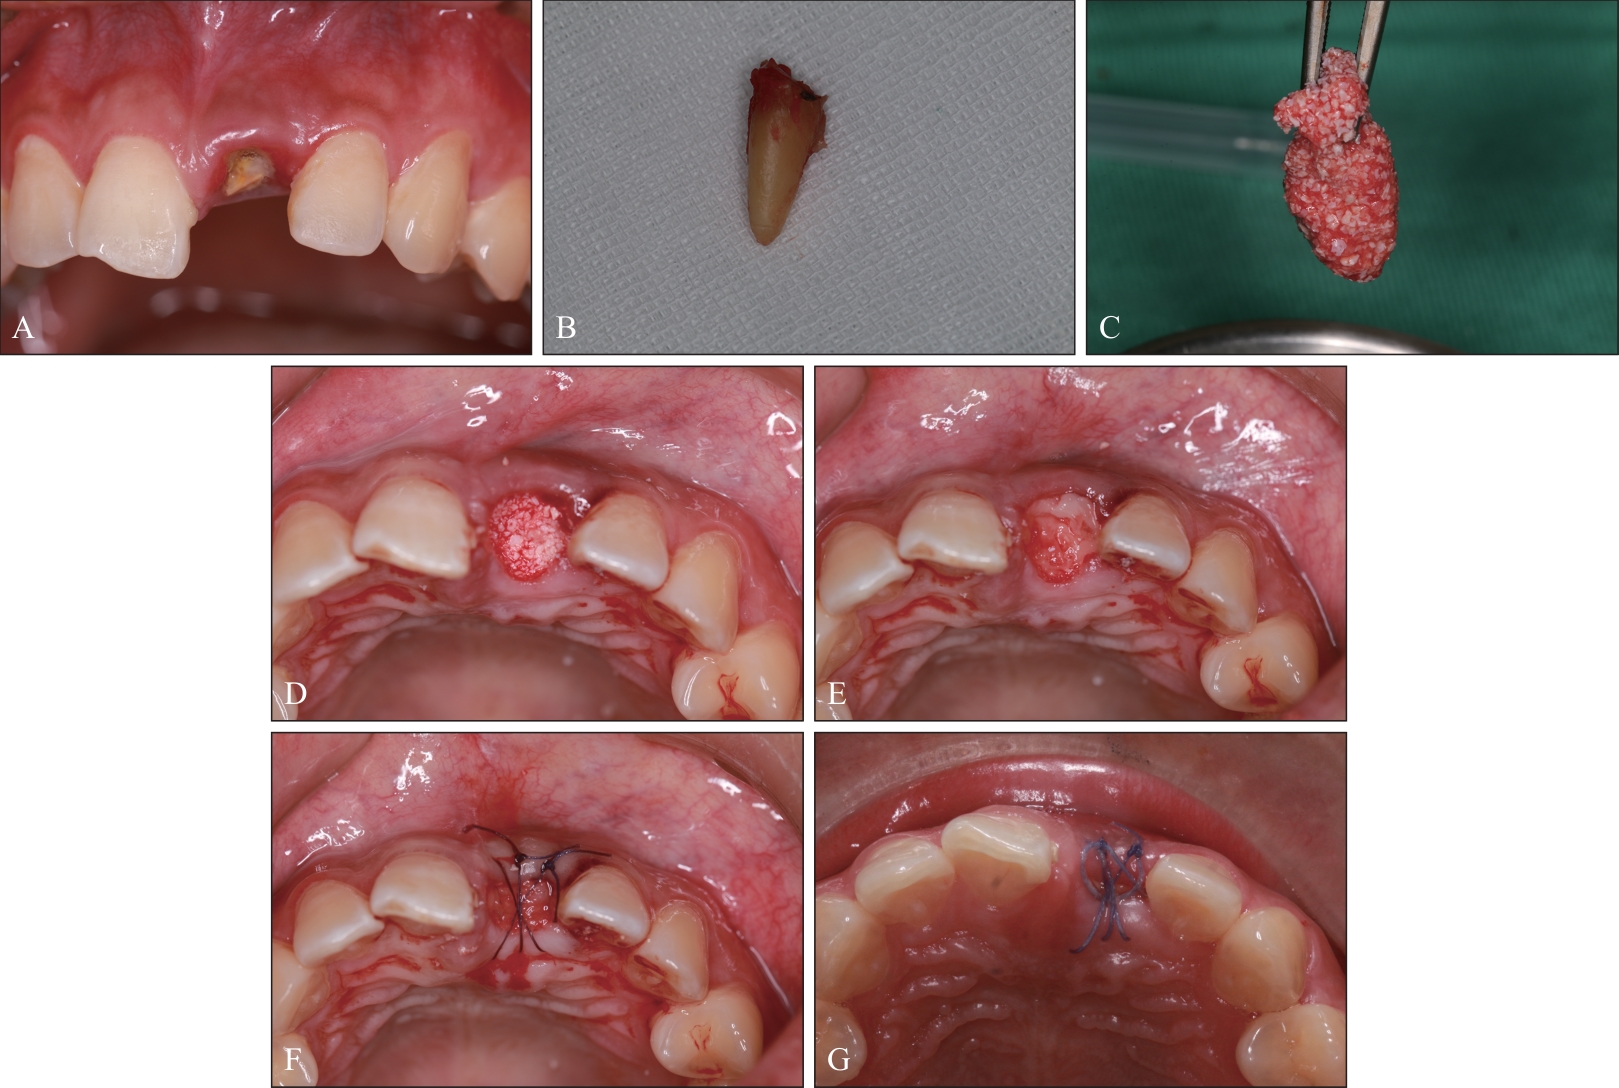

目的 比较浓缩生长因子(CGF)膜和Bio-Gide®胶原膜,分别与Bio-Oss®黏性骨联合用于上前牙牙槽嵴保存术(ARP)的临床效果。 方法 选取30例上前牙拔除后需要行ARP的患者,随机分为Bio-Gide组和CGF组。2组均在拔牙窝内严密充填Bio-Oss®黏性骨。Bio-Gide组用Bio-Gide®胶原膜覆盖于Bio-Oss®黏性骨上缘并封闭拔牙窝,CGF组用CGF膜覆盖并封闭拔牙窝。对比2组术后10 d软组织愈合情况,术后即刻及6个月牙槽嵴骨宽度及高度变化,以及术后6个月医患满意度。 结果 术后6个月,2组牙槽嵴骨宽度及高度变化差异无统计学意义(P>0.05)。但CGF组术后软组织愈合情况及医患满意度方面表现更优,差异有统计学意义(P<0.05)。 结论 与Bio-Gide®胶原膜相比,CGF膜与Bio-Oss®黏性骨联合应用可使上前牙ARP术后软组织愈合更好、医患满意度更高。

Objective To compare the clinical effects of concentrated growth factor (CGF) membrane and Bio-Gide ® collagen membrane, combined with Bio-Oss ® sticky bone respectively in alveolar ridge preservation (ARP) of maxillary anterior teeth. Methods Thirty patients who needed alveolar ridge preservation after maxillary anterior tooth extraction were selected and randomly assigned to the Bio-Gide group and the CGF group. In both groups, the extraction sockets were tightly filled with the Bio-Oss® sticky bone. In the Bio-Gide group used Bio-Gide® collagen membrane to cover the upper edge of the Bio-Oss® sticky bone and closed the wound. The CGF group, the CGF membrane was covered on the upper edge of the Bio-Oss® sticky bone and the wound was closed. The soft tissue wound healing status at 10 days after ARP, the changes in alveolar ridge height and width immediately after ARP and at 6 months after ARP, and the doctor-patient satisfaction at 6 months after ARP were compared and evaluated between the two groups. Results At 6 months after ARP, there was no statistically significant difference in the changes of alveolar bone width and height between the two groups (P>0.05). However, the CGF group showed better performance in soft tissue healing after ARP and doctor-patient satisfaction, and the differences were statistically significant (P<0.05). Conclusion Compared with the Bio-Gide® collagen membrane, the combined application of CGF membrane and Bio-Oss® sticky bone can lead to better soft tissue healing after ARP of maxillary anterior teeth and higher doctor-patient satisfaction, showing obvious advantages in ARP of maxillary anterior teeth.